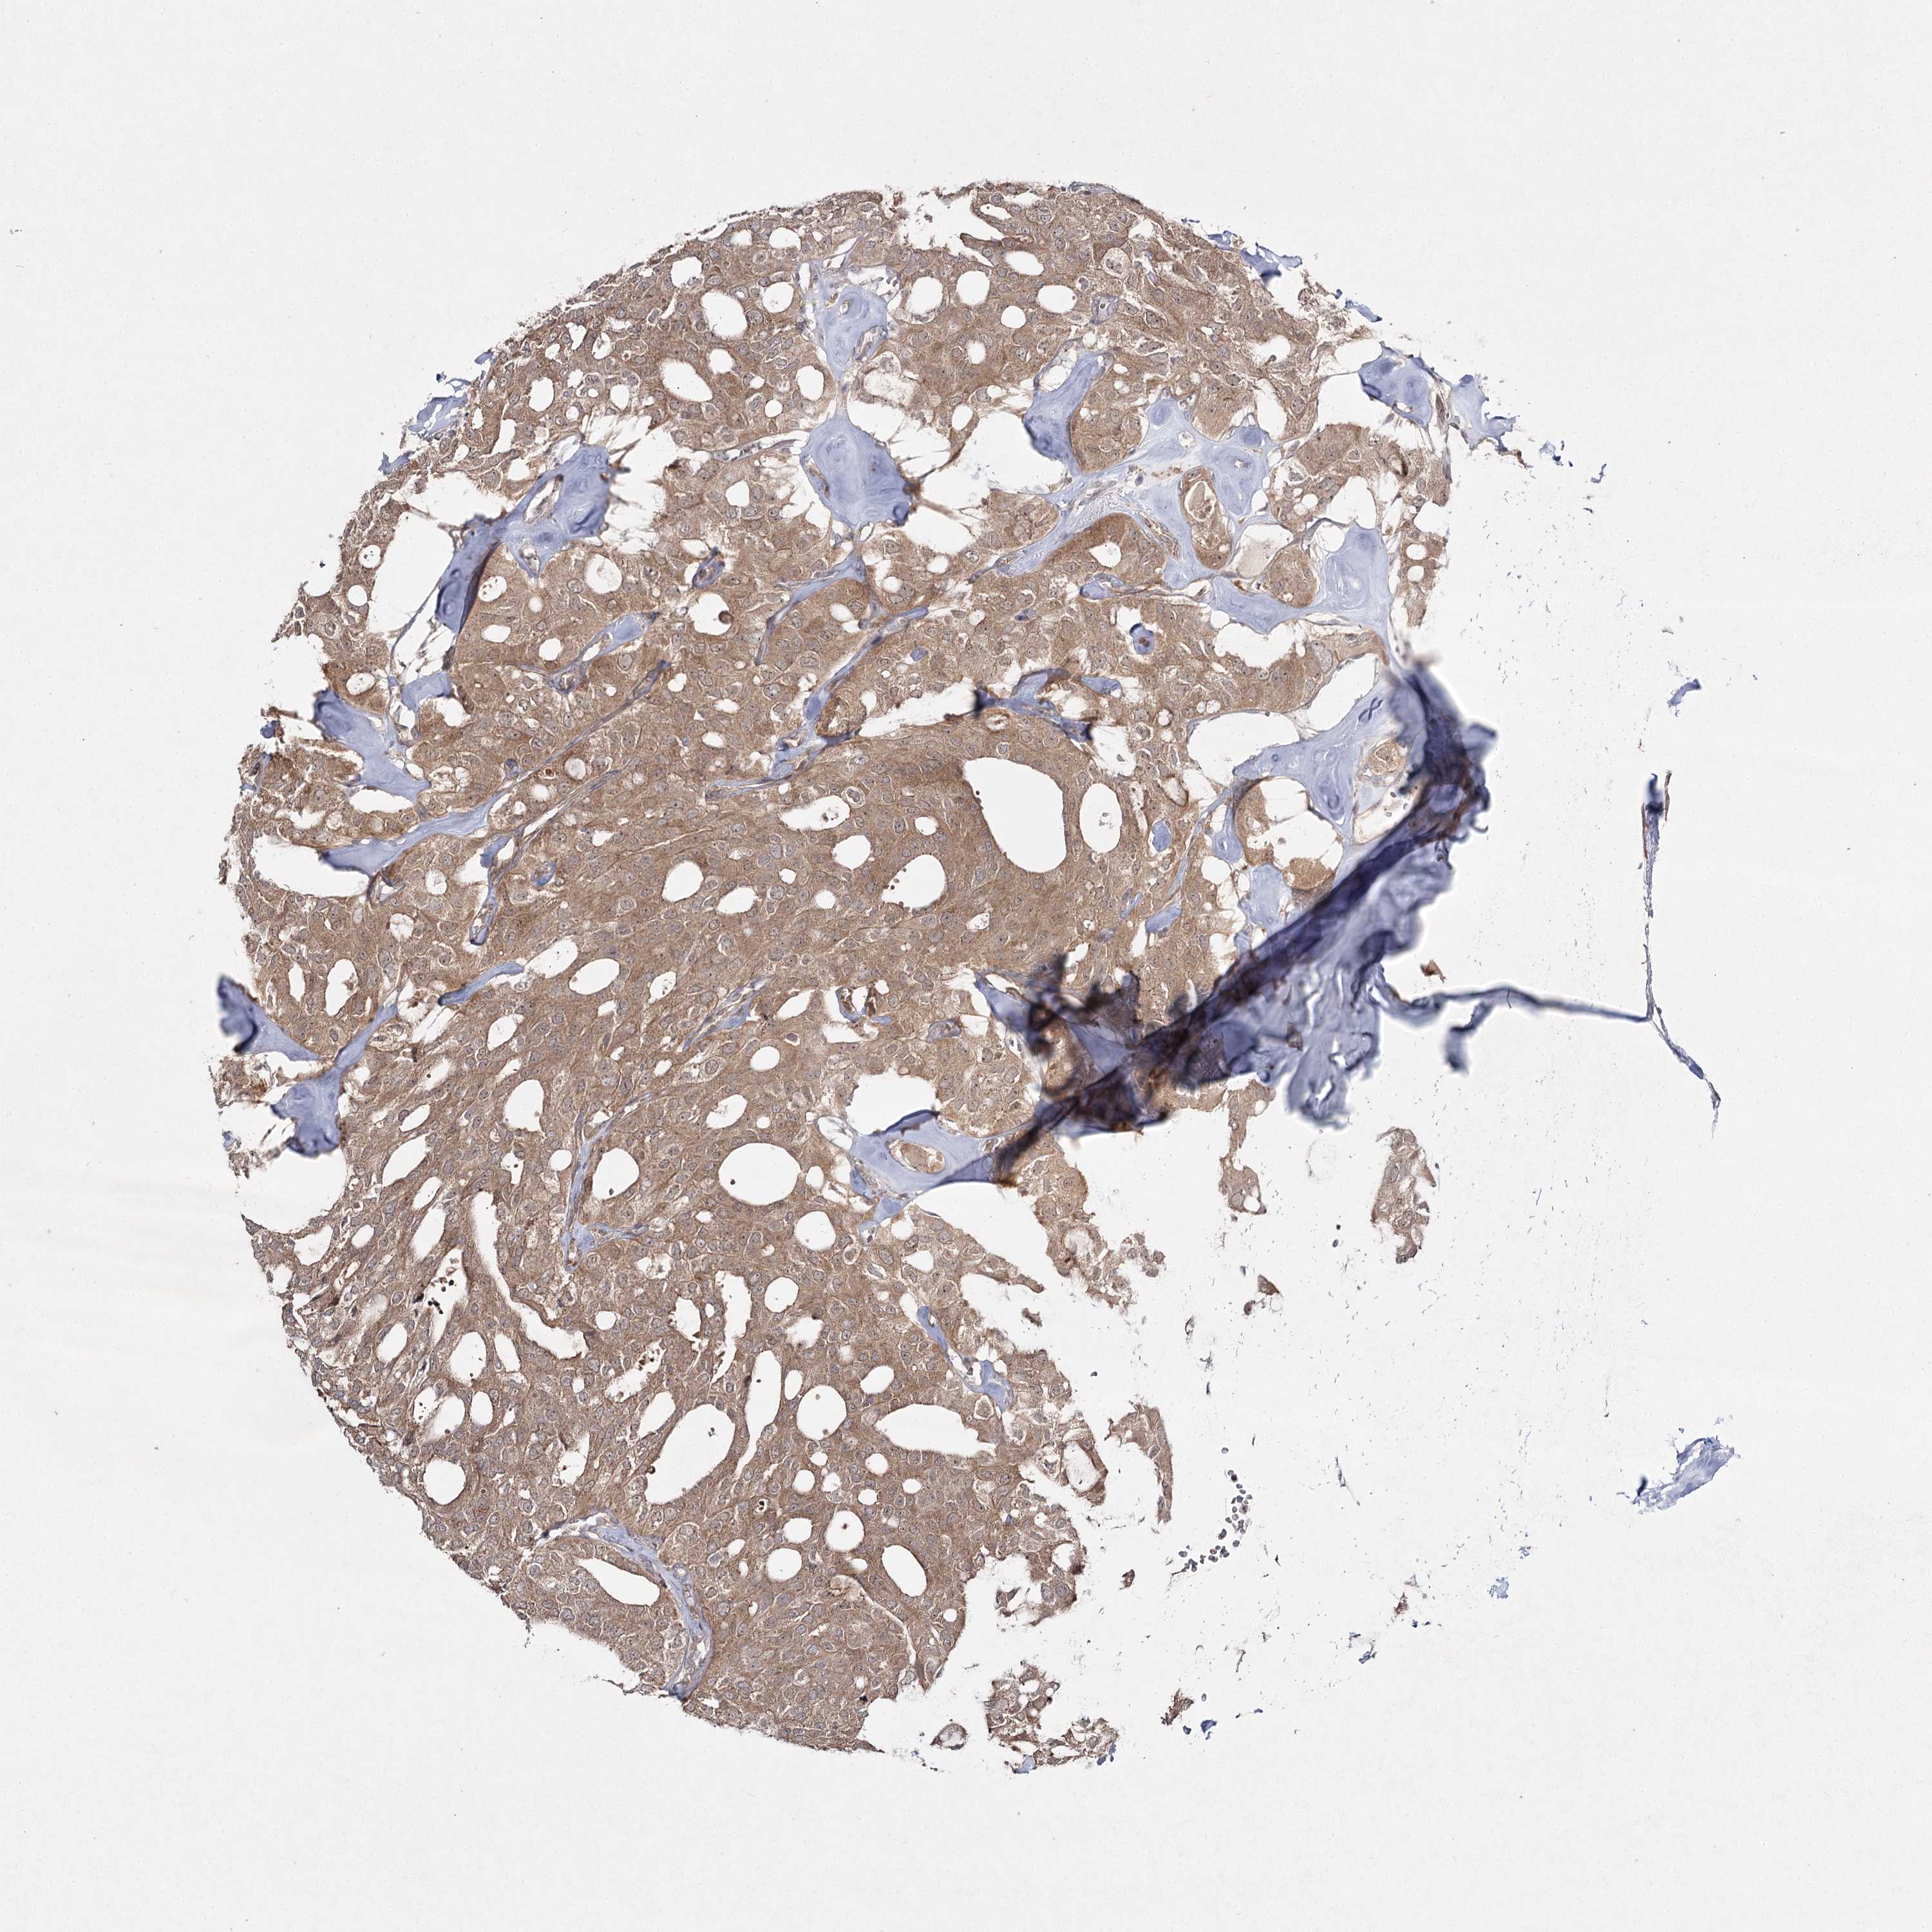

THYROID CANCER - Protein expressioni

A mouse-over function shows sample information and annotation data. Click on an image to view it in a full screen mode. Samples can be filtered based on level of antibody staining by selecting one or several of the following categories: high, medium, low and not detected. The assay and annotation is described here.

Note that samples used for immunohistochemistry by the Human Protein Atlas do not correspond to samples in the TCGA dataset.

Antibody stainingi

Antibody staining in the annotated cell types in the current human tissue is reported as not detected, low, medium, or high, based on conventional immunohistochemistry profiling in selected tissues. This score is based on the combination of the staining intensity and fraction of stained cells.

Each image is clickable and will lead to virtual microscopy that enables deeper exploration of all samples and also displays staining intensity scores, fraction scores and subcellular localization as well as patient and tissue information for each sample.

Antibody HPA038084

Staining

High

Medium

Low

Not detected

Intensity

Strong

Moderate

Weak

Negative

Quantity

>75%

75%-25%

<25%

None

Location

Nuclear

Cytoplasmic/membranous

Cytoplasmic/membranous,nuclear

Papillary adenocarcinoma, NOS

Follicular adenoma carcinoma, NOS